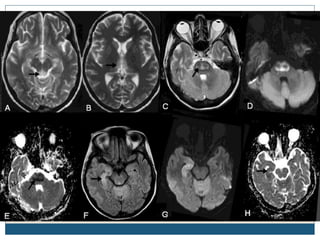

Typical MRI lesions

 Trident shaped / spreading bushfire pattern in central pons

 Signal characteristics of affected region include:

 T1: mildly or moderately hypointense

 T2: hyperintense, sparing the periphery and corticospinal tracts

 FLAIR: hyperintense

 DWI: hyperintense

 ADC: signal low or signal loss

 T1 C+ (Gd): usually there is no enhancement

 Radiologic findings do not improve over time, despite complete or nearly complete

clinical recovery

Typical MRI lesions Trident shaped / spreading bushfire pattern in central pons  Signal characteristics of affected region include:  T1: mildly or moderately hypointense  T2: hyperintense, sparing the periphery and corticospinal tracts  FLAIR: hyperintense  DWI: hyperintense  ADC: signal low or signal loss  T1 C+ (Gd): usually there is no enhancement  Radiologic findings do not improve over time, despite complete or nearly complete clinical recovery

Radiological differential diagnosisof CPM  General imaging differential considerations include:  demyelination - multiple sclerosis (MS)  infarction from basilar perforators can be central  pontine neoplasms - astrocytomas